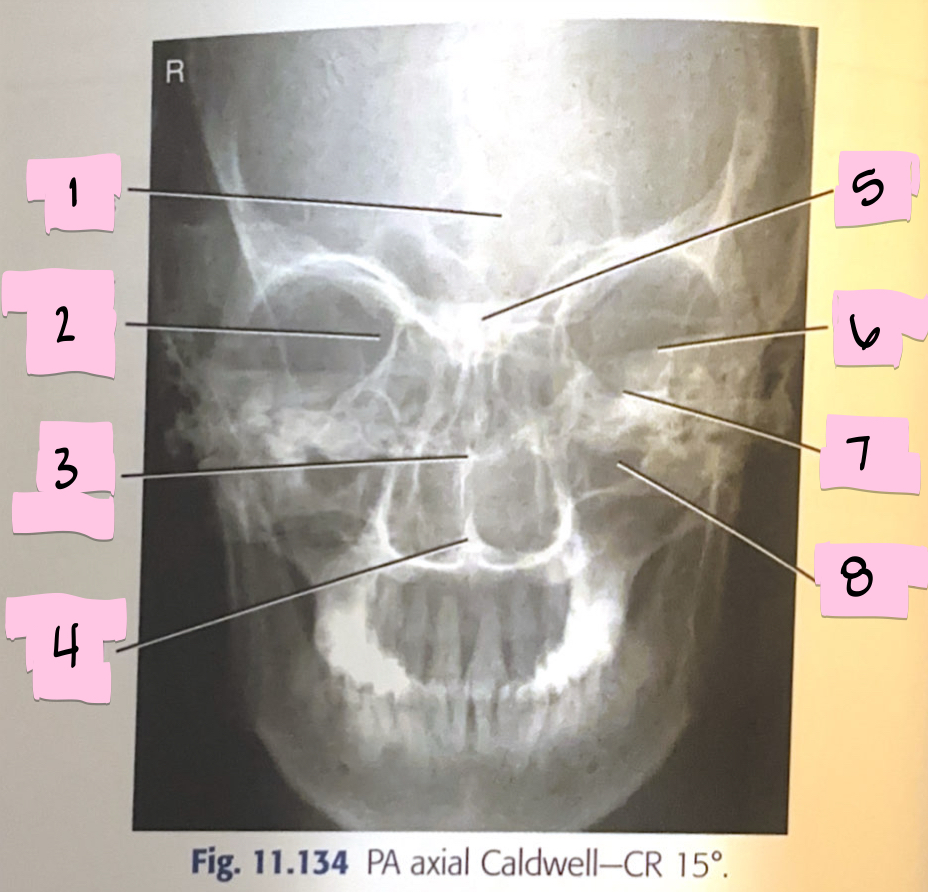

What is 1 pointing to?

Frontal sinus

What is 2 pointing to?

Superior orbital fissure

What is 3 pointing to?

Bony nasal septum

What is 4 pointing to?

Anterior nasal spine

What is 5 pointing to?

Crista galli

What is 6 pointing to?

Petrous ridge

What is 7 pointing to?

Floor of orbit

What is 8 pointing to?

Maxillary sinus